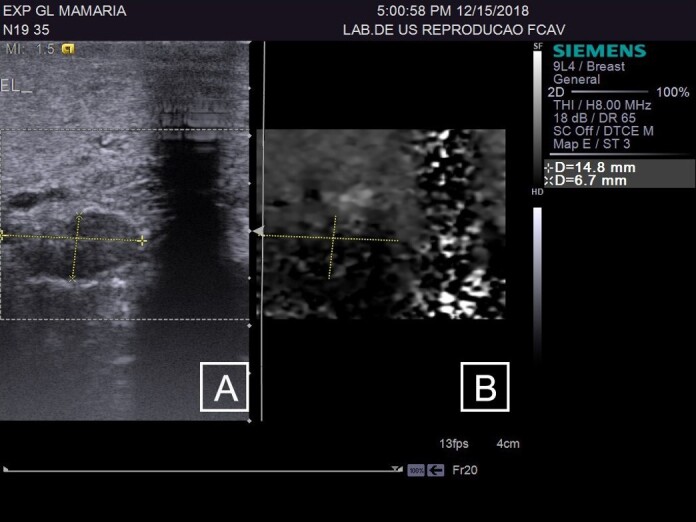

该研究旨在评估在乳腺实质和乳腺上淋巴结中使用Acustic Radiation Force Impulse(ARFI)弹性成像技术检测自然感染慢性纤维性病变绵羊活动性乳腺炎的情况。研究人员选取了 27 只雌性绵羊,采集了 48 个乳腺的 B 型超声波和 ARFI 弹性成像图像,获得了定性(回声和回声纹理)和定量(剪切率、深度和长短轴比)变量。这些乳腺被分为三个实验组:对照组(CG)--健康动物;LSCC--出现纤维性病变和 SCC(体细胞数)小于 500 x 103 cls/mL的动物;HSCC:出现纤维性病变和 SCC(体细胞数)大于 500 x 103 cls/mL的动物。在腺体的健康区域,LSCC 的剪切波速度(SWV)比 HSCC 高(P=0.04)。将 LSCC 组和 HSCC 组的纤维化部位与各自的正常部位进行比较时,两组的剪切波速度都有所增加:LSCC(p= 0.0007)和 HSCC(p= 0.0001)。将 LSCC 和 HSCC 的纤维化区域与 CG 实质进行比较,LSCC(p=0.001)和 HSCC(p=0.0001)的纤维化区域均有所增加。B 型超声显示,在活动性亚临床乳腺炎病例中,淋巴结以低回声为主,短/长轴比值降低。CG 组与 HSCC 组(P=0.02)和 GC 组与 LSCC 组(P=0.04)相比,乳腺上淋巴结的 SWV 增加。B 型超声波检查有助于评估乳腺实质,但不建议将其作为独立的诊断技术使用。ARFI 弹性成像显示了区分亚临床乳腺炎和痊愈乳腺炎的潜在临界点,突出了其作为区分正常区域和纤维实质区域工具的重要性。虽然由于样本量的限制,本研究没有确定具体的临界点,但更大样本量的进一步研究可以探索和确定这些关键临界点。

The aim of the study was to evaluate the use of Acustic Radiation Force Impulse (ARFI) elastography in mammary parenchyma and supramammary lymph nodes, for detection of active mastitis in sheep with naturally infected chronic fibrous lesions. 27 female sheep were included and B-mode ultrasound and ARFI elastography images were obtained, acquiring qualitative (echogenicity and echotexture) and quantitative (shear rate, depth and short/long axis ratio) variables of 48 mammary glands. The glands were divided into three experimental groups: control group (CG) - healthy animals; LSCC- animals that presented fibrous lesions and SCC (somatic cell count) less than 500 x 103 cls/mL; HSCC: animals that presented fibrous lesions and SCC (somatic cell count) more than 500 x 103 cls/mL; The qualitative variables using B-mode ultrasonography, including echotexture and echogenicity, showed no significant differences between the evaluated groups and tissues (p = 0.9336 and p = 0.233, respectively) .In healthy areas of the gland, it was an increasing in shear wave velocity (SWV) in LSCC than in HSCC (p=0.04). When comparing the fibrosis in the LSCC and HSCC groups with their respective normal areas, the velocity increased in both groups: LSCC (p= 0,0007) and HSCC (p= 0,0001). When comparing the areas of fibrosis in LSCC and HSCC with the CG parenchyma, there was an increase in LSCC (p=0.001) and HSCC (p=0.0001). B-mode ultrasound indicate predominance of hypoechoic echogenicity in lymph nodes and reduced short/long axis ratio in cases of active subclinical mastitis. The supramammary lymph node showed increased SWV when comparing the CG with HSCC groups (p=0.02) and GC with LSCC (p=0.04). B-mode ultrasonography is useful for evaluating the mammary parenchyma, however, its application as a standalone diagnostic technique is not recommended. ARFI elastography indicates potential cutoff points for differentiating subclinical mastitis from healed mastitis, highlighting its importance as a tool for distinguishing normal areas from fibrous parenchymal areas. While this study did not establish specific cutoff points due to sample size limitations, further research with larger sample sizes could explore and define these critical thresholds.